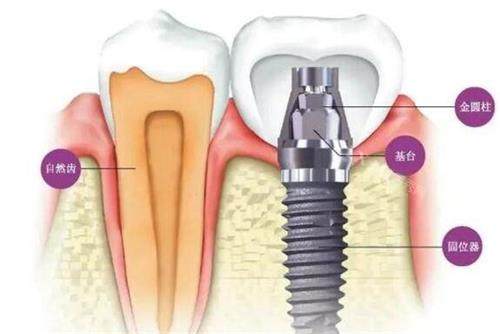

种植牙系列

韩国迪耀种植体:2878-5980元/颗(高性价比首要选择)

韩国登腾种植体:2890-12800元/颗(临床使用率高)

韩国奥齿泰种植体:8000元起/颗

美国进口种植体:9000元起/颗

瑞典诺贝尔PMC种植体:5577-15800元/颗(骨条件适配型)

瑞典诺贝尔种植体:15000-22000元/颗(高端稳定型)